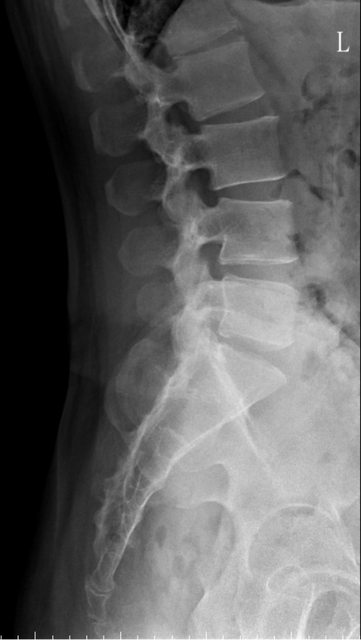

https://i.imgur.com/9HfkOHc.png

https://i.imgur.com/7NtJDKg.png

醫生似乎很急 就問了二個問題就叫我去照X光 可能就一分鐘吧 回來看了下X光就說可能有神經壓迫 又是14天的消炎止痛藥 說還會痛再來回診或去看脊柱專科或復健科 感覺就是浪費了一天的時間排隊再排隊 沒得到答案 也沒有得到解決... 然後拿了吃越多可能洗腎越快的止痛藥 會不會下次脊柱專科也開14天消炎止痛說如果還有問題叫你去掛神經科? 為何不給我照MRI呢?我第一次去看問了MRI就還是只給我照X光 1.2期X光照了也不一定有異常,我實在不懂不用MRI的邏輯 體驗實在太差了,當然我也知道當有一百號排隊時問診就不可能細到哪怕只有15分 我想不等直接掛看看禮拜三神經科會怎解釋了 ※ 編輯: capybaradash (118.166.44.25 臺灣), 07/31/2023 14:29:17 ※ 編輯: capybaradash (118.166.44.25 臺灣), 07/31/2023 14:37:27

看了下治療方法,那有看等於沒看了 照MRI似乎也是白做,自費照根本浪費 其實X光以我外行人放大好幾倍看過去,左股骨跟大腿骨明顯狀態較差 不清楚醫生是不是有鷹眼,小小一張看過去就說沒什問題 我是不會去考慮手術的 小時候骨折都是看國術館 還減壓股頭打孔...開刀100%NO 治療方法 1.拐杖 2.藥物治療(1)非類固醇類消炎止痛藥(NSAID) (2)口服雙磷酸鹽類藥物 (3)血管擴張劑 (4)高壓氧 目前股骨頭缺血性壞死的治療,根據現有的證據,仍然以手術為主流。 於早期(第一、二期),尚未塌陷的股骨頭缺血性壞死,髖關節減壓手術值得一試, 至於第三、甚至第四期股骨頭缺血性壞死,人工髖關節置換術能夠有效的解除疼痛以及恢 復行走負重的功能。 ※ 編輯: capybaradash (118.166.44.25 臺灣), 07/31/2023 16:04:20

g17321732: 1.骨頭看起來沒大問題,x光不是放大找不一樣這麼簡單 07/31 18:18

g17321732: 3.MRI對你的幫助不大,X光已經足夠清楚,不用花冤枉錢 07/31 18:18